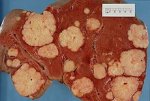

«бычье сердце»Когда люди говорят о том, что у кого-то «бычье сердце», то имеется в виду здоровое сердце, умеющее переносить... «бычье сердце»Когда люди говорят о том, что у кого-то «бычье сердце», то имеется в виду здоровое сердце, умеющее переносить...